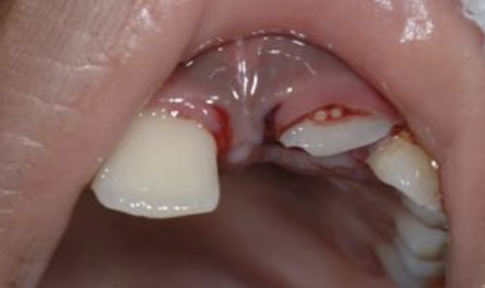

Examen endobuccal :

А̀ vérifier :

• Gencive, muqueuse, lèvres (morsure / plaie) ;

• Os alvéolaire (fracture) ;

• Dents : concernées directement / collatérales / antagonistes / postérieures / occlusion ;

> Mobilité : attention chez l’enfant physiologique ;

> Pas de test de vitalité ni de sensibilité car peu objectifs à ces âges-là !